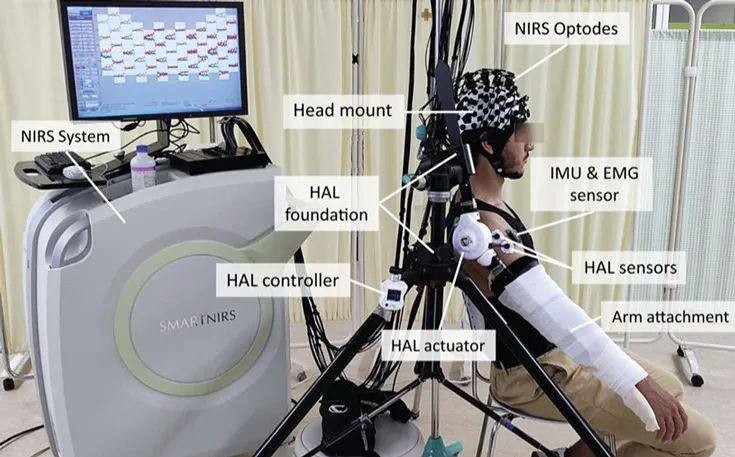

自带的NIRS探头

项目类型

器械质押区

起投金额

15000USDT

每日释放:0.86

释放周期:31 天

已购: 1333

剩余: 0